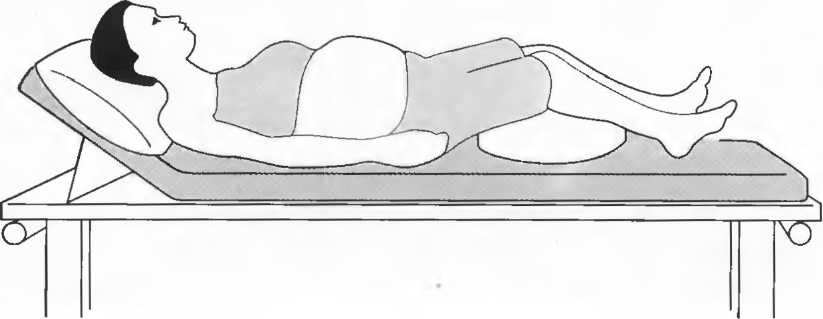

Подготовка

1. Подготовка